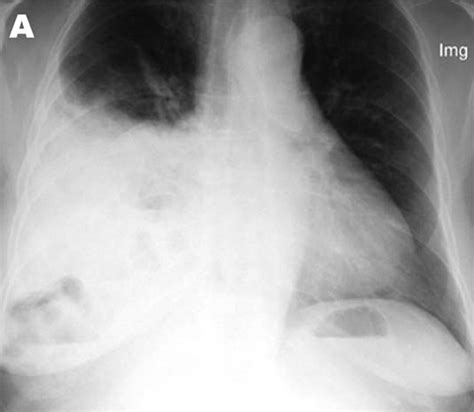

Chest X-ray: Provides a basic view of the chest and can show the presence of a hernia.

CT Scan: Offers detailed images of the chest and abdomen, helping to identify the location and size of the hernia.